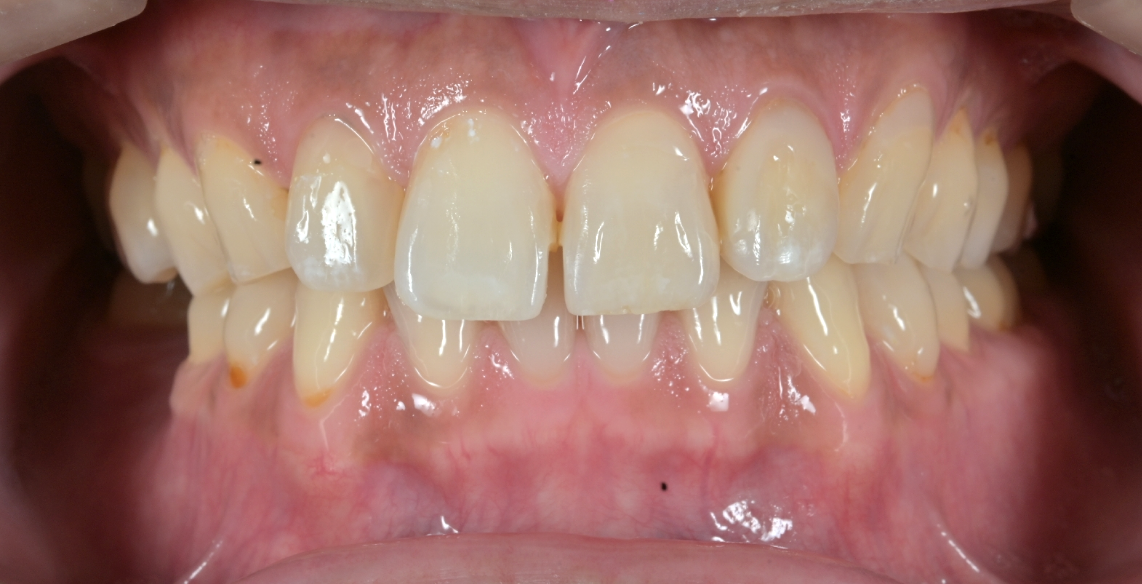

また、ホワイトニングにもご興味があるということだったのでアイコン治療を始める前にホワイトニングもされ、前歯だけではなく全ての歯を白くきれいに改善されてます!

After

・治療した歯がわからないくらい自然な仕上がりに